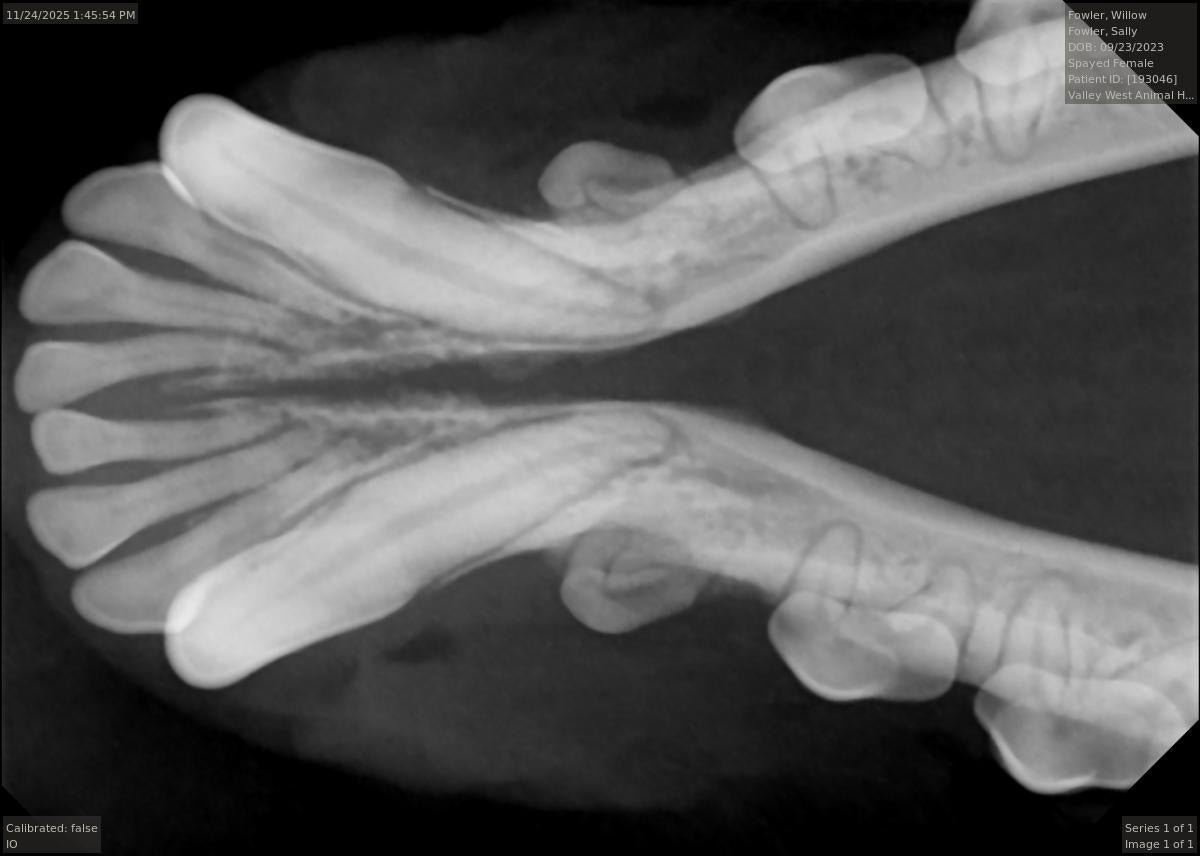

In order to remove this tartar, we perform dental scaling, our most basic dental procedure. During the scaling process our practice uses sonic and ultrasonic power scalers as well as hand held instruments to remove this tartar from the surface of the teeth both above and below the gum line.

Tooth extraction is another very common procedure. It is the goal of our practice for your pet to retain as many teeth as possible. However, sometimes extraction is the only option to relieve pain or ensure that periodontal disease does not advance. If not extracted, many times a diseased tooth can compromise the surrounding tissue and neighboring teeth. If caught early, there are more treatment options available for periodontal disease.